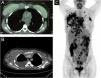

Chest CT scan, along with a whole-body PET/CT, revealed a liquid collection surrounding the right mammary implant, with an increase in soft tissues in the chondrosternal joint, poor definition of the pectoral planes in its medial portion, and trabeculation of subcutaneous fat. In contrast, multiple pathological adenopathies were observed in the anterior mediastinum, bilateral axillary regions, and supraclavicular fossae (Fig. 2A‒C).

(A‒B) Liquid collection surrounding the right mammary implant, with an increase in soft tissues in the chondrosternal joint, poor definition of the pectoral planes in its medial portion, and trabeculation of subcutaneous fat. (C) Multiple pathological adenopathies were observed in the anterior mediastinum, and bilateral axillary regions and supraclavicular fossae.